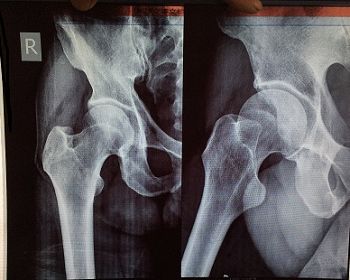

二零一七年四月二十六日,这个邻居腿腰痛的受不了了,就去医院,结果医生拍的片子是脊骨下五段不直了,骨头增生,右大腿钻轴不圆了。邢台治不了,得去北京军医院手术。

'邻居右大腿钻轴片'

邻居右大腿钻轴片